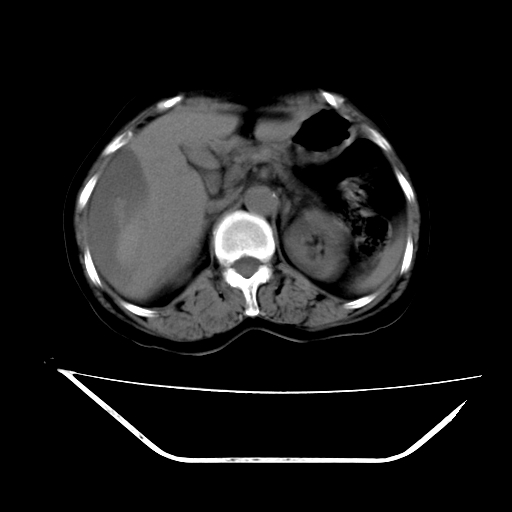

2008-11-10ct平扫(其间去中山医院诊治未行特殊治疗)

2008-11-10ct平扫见并肝内、血膜下血肿基本吸收,肝内低密度灶缩小。此时再做增强ct应有显着意义。对患者/医者都好!

从平扫+增强及治疗后复查片,病变明显缩小,不考虑肝癌出血可能,还是考虑为良性病变可能性大;单纯血肿并包膜下积液吧,病变强化没法解释,肝血管破裂出血吧,增强不符合典型血管瘤的表现,良性肿瘤破裂出血吧,复查片看来好像也不太支持(没做强化也不太好说)。本人还是考虑单纯肝内血肿并包膜下积液,强化是不是血管有外渗。

患者自6月至11月,如果是肝癌,没有经过特殊治疗,想必应该会有所进展吧,而不是ct所见,反而似有病灶减小的趋势。建议增强。

病变破裂出血应首先考虑,病变性质即可能是恶性也可能是良性,楼主说患者到上级医院检查未见癌细胞,以良性可能性大,首先考虑腺瘤破裂出血可能。

追问病史,患者有过度用力病史,当时立即感腹痛;所以还考虑肝破裂可能性大。